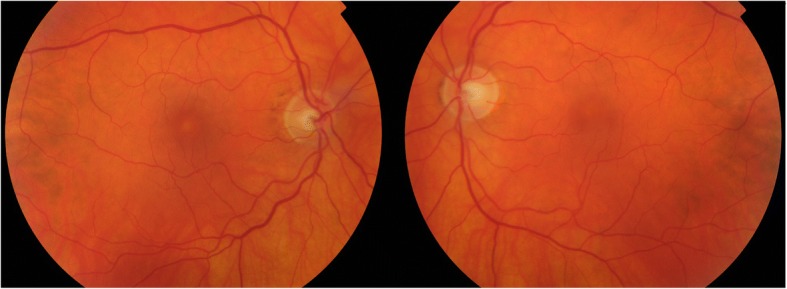

Fig. 2.

Fundus appearance: Healthy optic disc, dull foveal reflex and normal vasculature